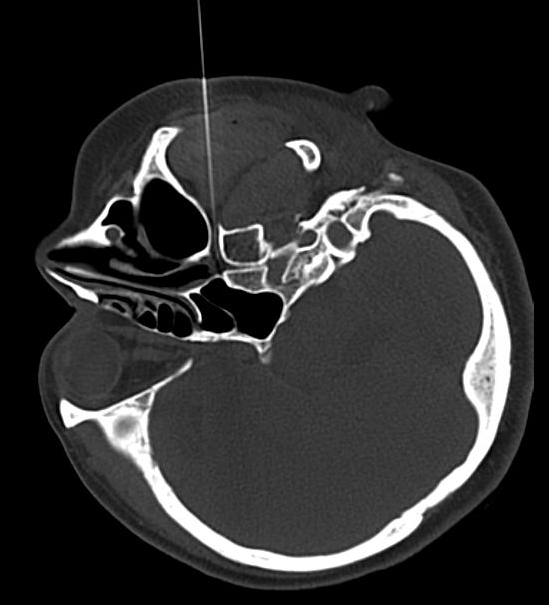

由于肿胀或水肿的鼻粘膜阻塞了在中鼻道和上鼻道的鼻窦开口所致。几乎所有的过敏性鼻炎患者均有不同程度的过敏性鼻窦炎,受侵的鼻窦常为双侧或全鼻窦。过敏性鼻炎在没有继发感染前,常无明显的临床表现,诊断依靠鼻窦X线摄片或CT扫描。

在CT引导下蝶腭神经节射频治疗,手术后有效率达95%以上。优势是: